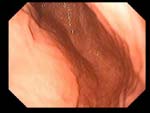

Гастроэзофагеальная рефлюксная болезнь Гастроэзофагеальная рефлюксная болезнь

Рефлюкс-эзофагит

Пациент З., 24 года.

Рефлюкс-эзофагит I ст., дуодено-гастральный рефлюкс, эритематозная гастропатия, эритематозная дуоденопатия.

Эндоскоп GIF - V70 во время акта глотания свободно введен в пищевод. Пищевод свободно проходим. Z-линия - 38 см от резцов. Складки продольные, просматриваются на всем протяжении. В н/3 пищевода (верхняя граница - 35-36 см от резцов) - диффузная эритема, проксимальнее Z- линии - 1 эрозия неправильной формы в пределах одной складки. Розетка кардии сомкнута. Содержимое желудка - мутное, с примесью желчи, избыточное количество. Слизистая оболочка свода, в/3 тела диффузно гиперемирована, диффузно отечна. Слизистая оболочка с/3, н/3 тела и антрального отделов диффузно отечна, очагово гиперемирована. Привратник сомкнут. Луковица 12 п.к. правильной формы, расправляется при небольшой инсуффляции воздуха. Содержимое - мутное с примесью желчи, скудное. Слизистая оболочка умеренно очагово гиперемирована, контактно ранима в области передней стенки. Залуковичные отделы: содержимое мутное, пенистое, с примесью желчи. Слизистая оболочка умеренно диффузно отечна, умеренно очагово гиперемирована.